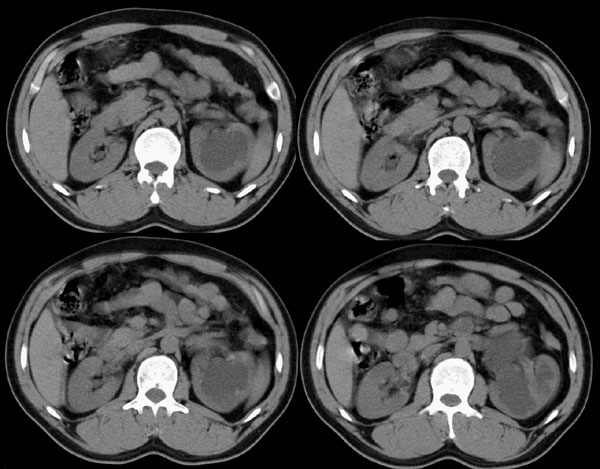

左侧肾盂、肾盏扩张,肾盂输尿管移行部突然狭窄,未见明显占位及高密度结石影,体检发现,考虑:先天性肾盂输尿管移行部狭窄。(原因多方面,有先天缺陷造成移行部结构异常或因为迷走血管、纤维索条引起肾盂输尿管的压迫扭曲所致。)大剂量ivp或肾盂造影有助于显示输尿管狭窄部位及形态。

就是简单的左肾盂积水,原因很可能是肾门部的血管压迫所致,建议做多期增强

左肾积水(原因待查),不排除左肾盂输尿管移行部迷走血管压迫所致可能。